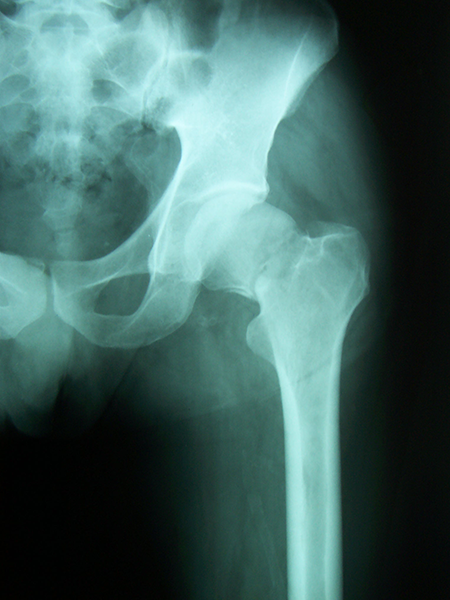

Case:9 Comminuted Intertrochanteric Fracture

Patient aged 75 years with Comminuted Intertrochanteric fracture treated with closed reduction & Ender’s nailing.

Pre-op Ap

Pre-op Lateral